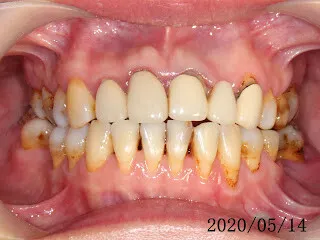

假牙材質2臨床案例...不同的假牙材質+牙齦萎縮